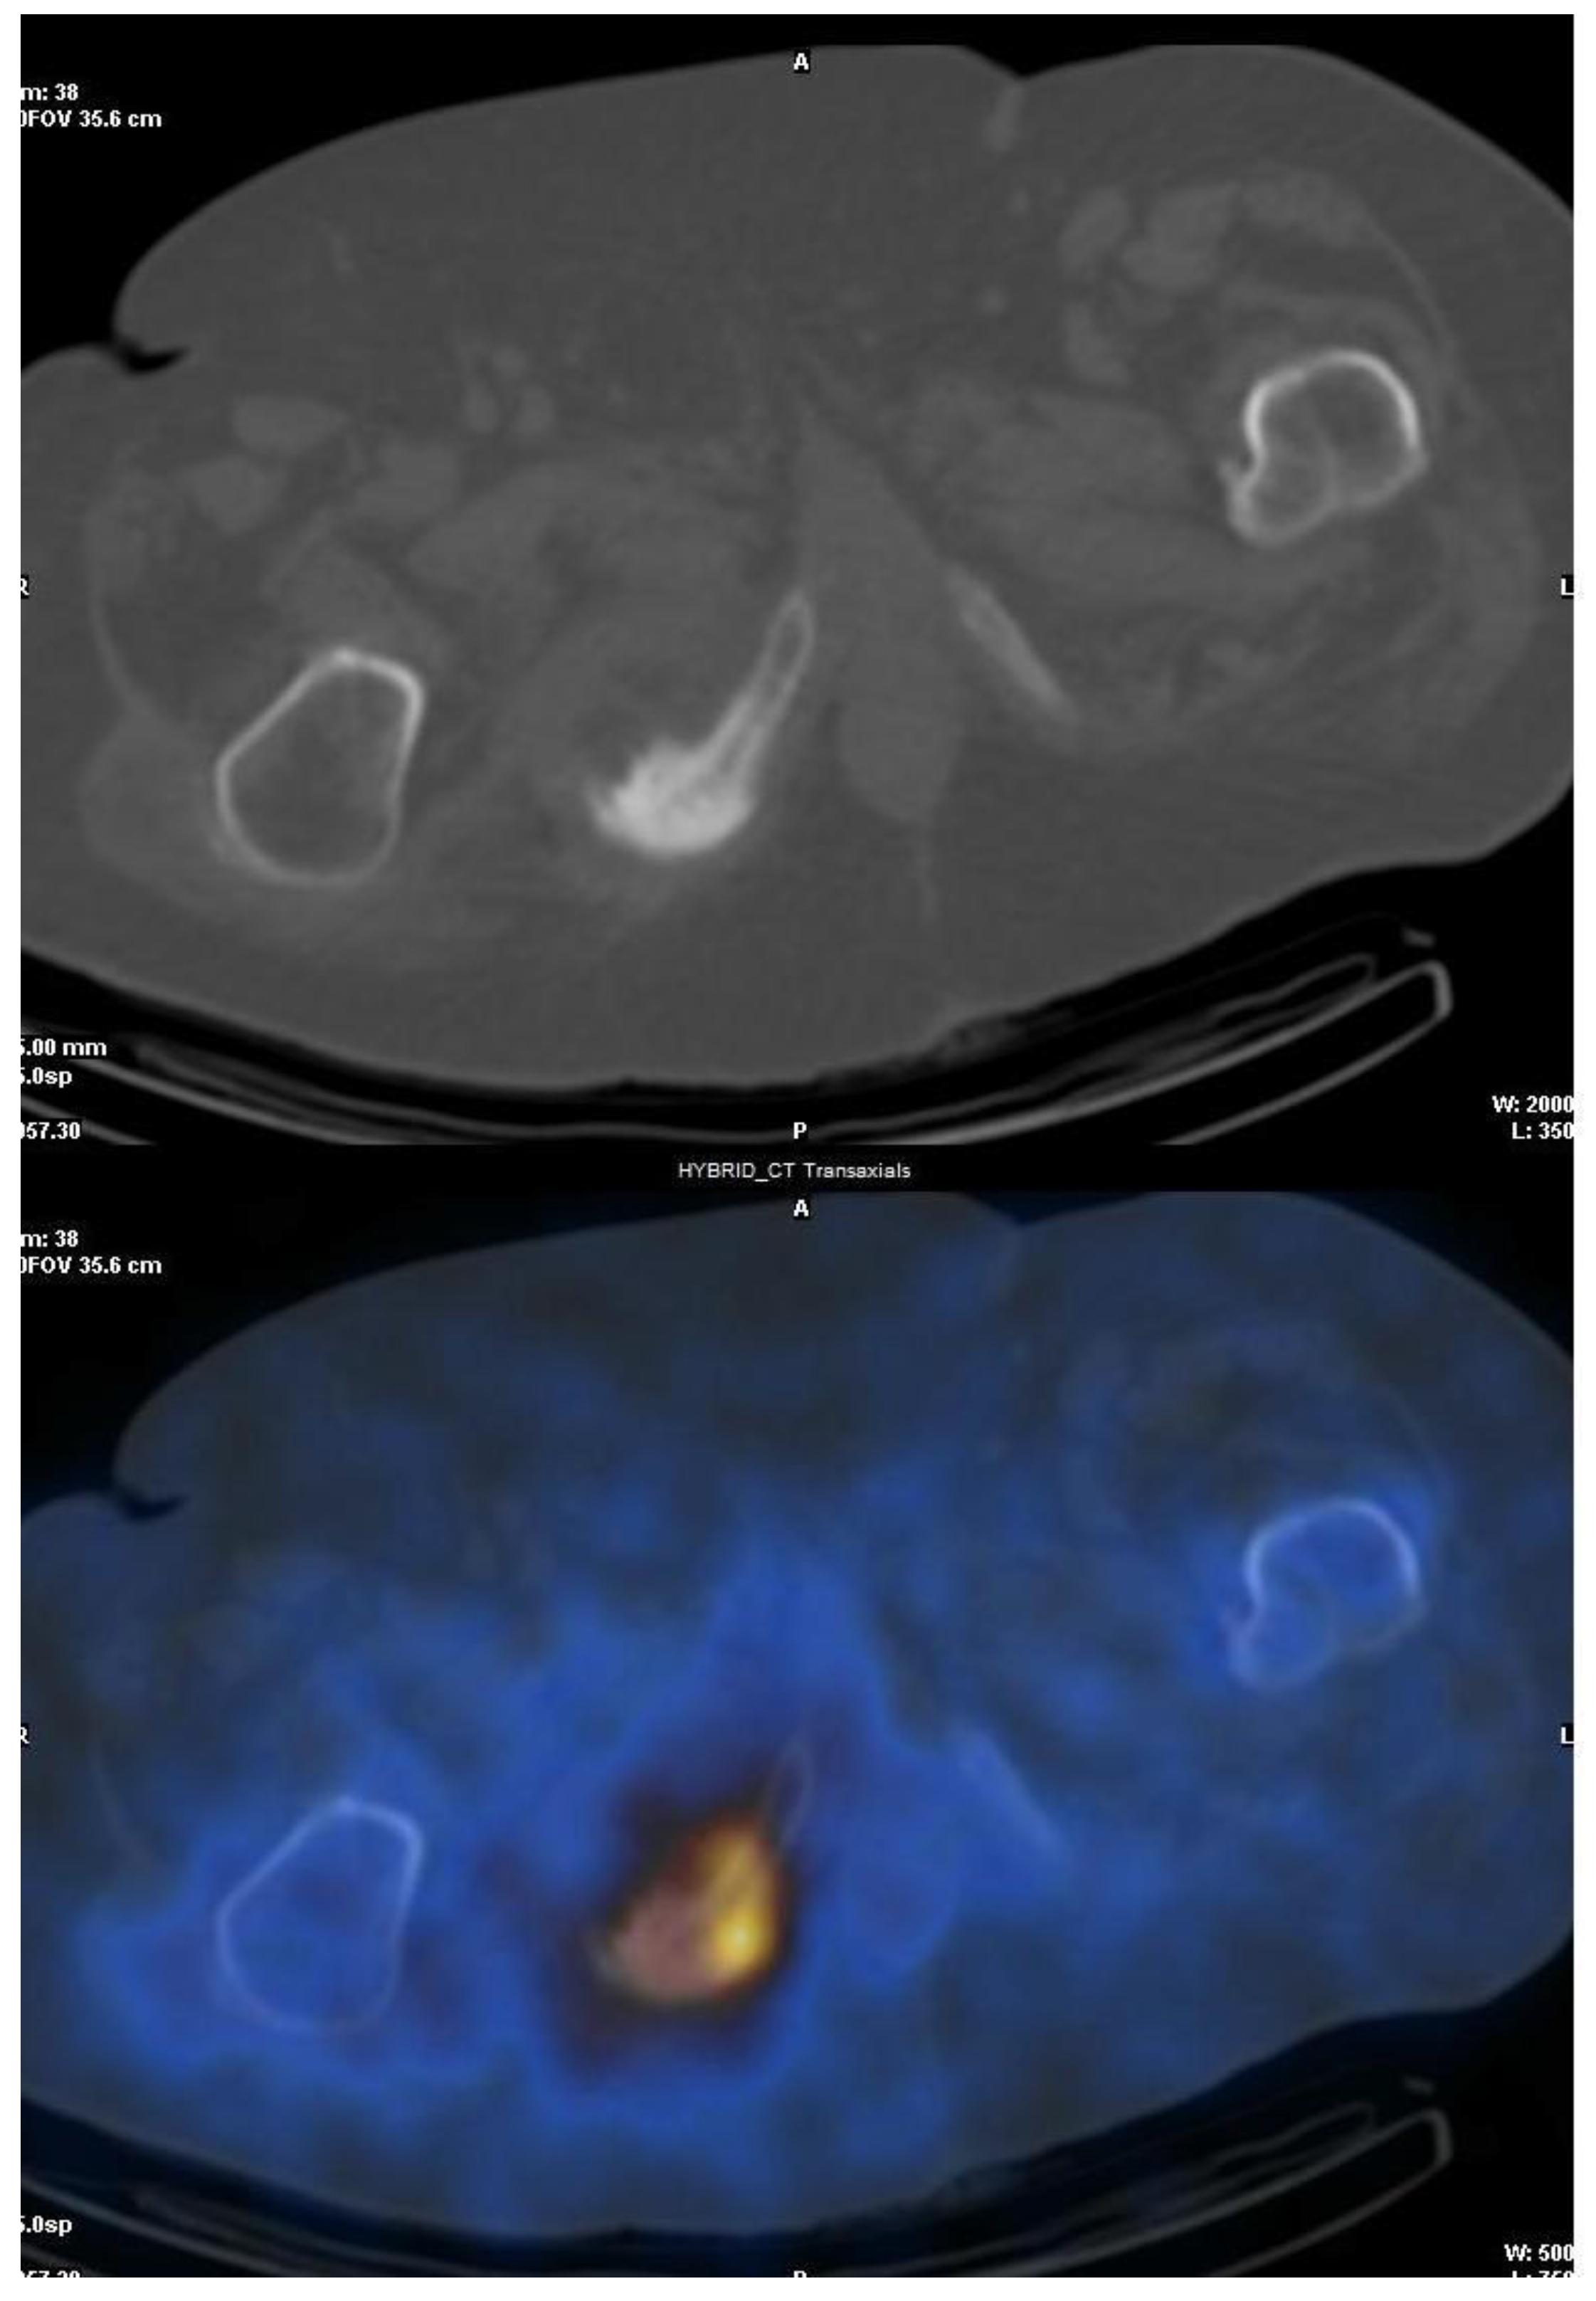

3.1. SPECT/CT plus 99mTc, 67Ga or Labeled Leucocyte Scintigraphy

- Domínguez, M.L.; Lorente, R.; Rayo, J.I.; Serrano, J.; Sánchez, R.; Infante, J.R.; García, L.; Durán, C. SPECT-CT with 67Ga-citrate in the management of spondylodiscitis. Rev. Esp. Med. Nucl. Imagen Mol. 2012, 31, 34–39. [Google Scholar] [CrossRef] [PubMed]

- Fuster, D.; Solà, O.; Soriano, A.; Monegal, A.; Setoain, X.; Tomás, X.; Garcia, S.; Mensa, J.; Rubello, D.; Pons, F. A prospective study comparing whole-body FDG PET/CT to combined planar bone scan with 67Ga SPECT/CT in the Diagnosis of Spondylodiskitis. Clin. Nucl. Med. 2012, 37, 827–832. [Google Scholar] [CrossRef] [PubMed]

- Liévano, P.; De la Cueva, L.; Navarro, P.; Arroyo, E.; Añaños, M.; Abós, M.D. SPECT-TAC de baja dosis con 67Ga en un caso de espondilodiscitis y hernia de Schmorl. Rev. Esp. Med. Nucl. 2009, 28, 288–290. [Google Scholar] [CrossRef]

- Thang, S.P.; Tong, A.K.; Lam, W.W.; Ng, D.C. SPECT/CT in musculoskeletal infections. Semin. Musculoskelet. Radiol. 2014, 18, 194–202. [Google Scholar] [CrossRef] [PubMed]